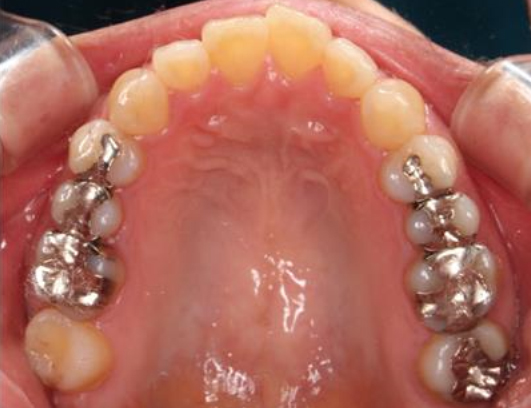

銀歯の詰め物・被せ物を、e-maxのインレーやクラウンに置き換えた症例。